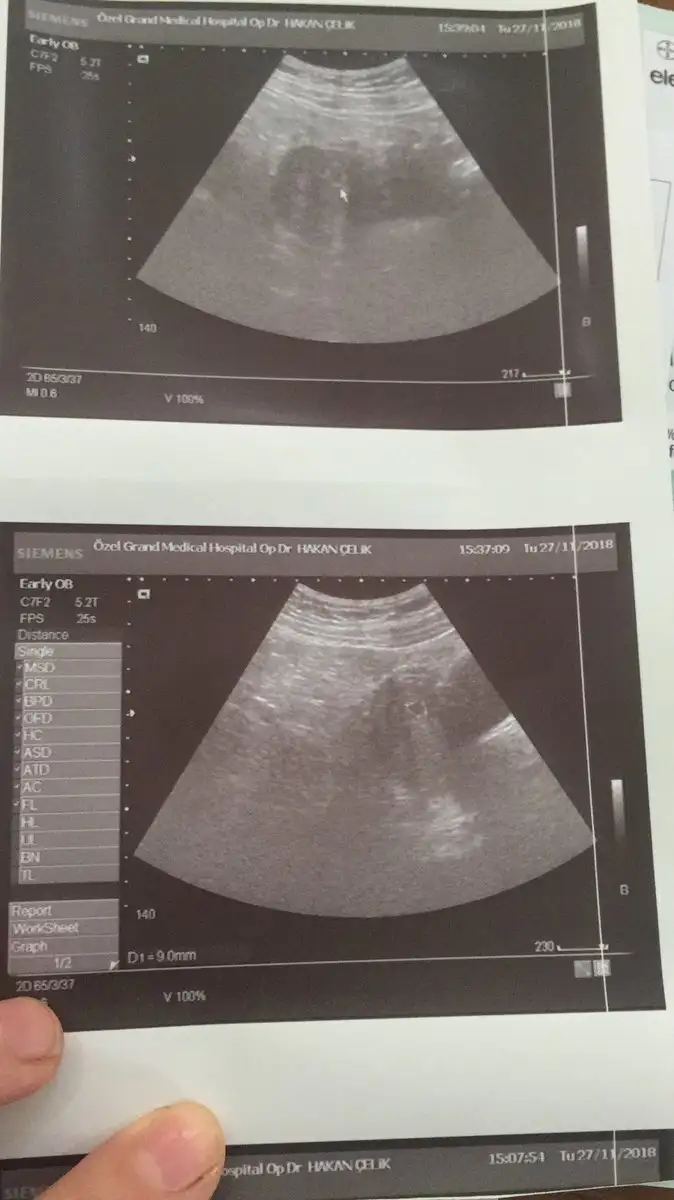

Merhaba kizlar bu gün kesem gözüktü 4+6 dedi doktor burdan biri kese hangi taraftaysa ona göre cinsiyet tahmin ediyordu kimdi o

Eklentiler

• 21C70EF8-FDCE-419D-855C-3E9D7842D1C5.webp

21C70EF8-FDCE-419D-855C-3E9D7842D1C5.webp

27,1 KB · Görüntüleme: 45

• 48E4F86F-D574-4D35-9ABA-B5A04B8A0741.webp

48E4F86F-D574-4D35-9ABA-B5A04B8A0741.webp

29,4 KB · Görüntüleme: 53

• 561EC29F-59CA-4966-A730-A51A0998CE40.webp

561EC29F-59CA-4966-A730-A51A0998CE40.webp

42,8 KB · Görüntüleme: 50